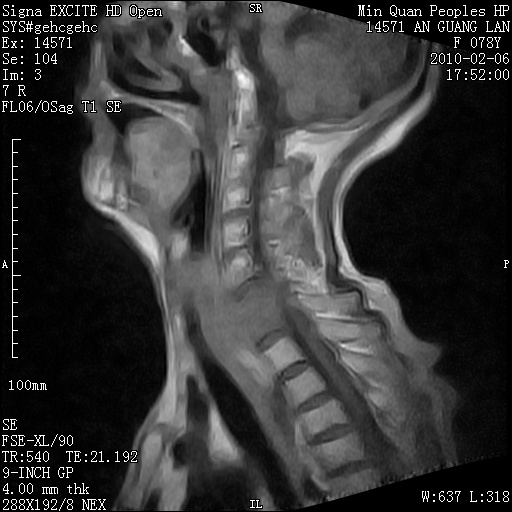

标题: MRI2763:C6、C7椎体病变性质?

f,78y,颈部与双上肢阵发性剧痛40余天。ct可见c6、c7椎体虫蚀样破坏,其间椎间隙变窄(没有图片资料可供上传)。

考虑椎体结核并椎旁脓肿。

考虑:c6/7椎体结核并椎旁脓肿形成,建议增强扫描。